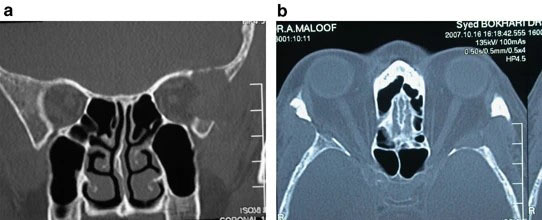

これは術後のCTを示した論文のFigureです。Eye (Lond)という論文に掲載されたものですが、外壁の骨が無くなっているのが分かると思います。これに加えて眼窩脂肪を適宜切除するのがLateral wall decompressionであり、当院もこれに倣った方法で手術を行っています。

M J Millar 1, A J Maloof. The application of stereotactic navigation surgery to orbital decompression for thyroid-associated orbitopathy. Eye(lond) 2009 Jul;23(7):1565-71